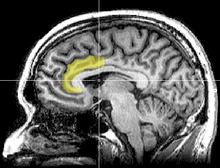

A study from the University of Sussex (UK) compared the brain structure of participants with the amount of time they spent on media devices i.e. texting or watching TV. [1]

The MRI scans of the participants, showed that the high multitaskers had less brain density in the anterior cingulate cortex. This is the brain region responsible for empathy and emotional control.

The implication of their findings, is that multitasking, especially involving the use of media devices, could permanently alter brain structure after a long period of usage.

Bradberry suggests that multitasking could damage the part of the brain — anterior cingulate cortex — responsible for emotional intelligence.